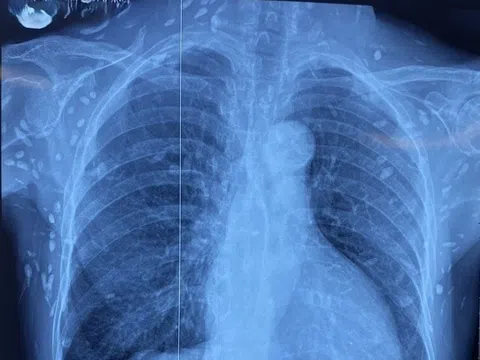

Ung thư vú có thể phát hiện sớm thông qua siêu âm màu tuyến vú

- MRI tuyến vú: đây là phương tiện đặc biệt trong việc phát hiện những biểu hiện phức tạp của ung thư vú. Chụp MRI vú với thuốc cản từ thế hệ mới cho kết quả hình ảnh bên trong vú rõ ràng hơn, phát hiện ra ung thư mà chụp X-quang tuyến vú có thể bỏ sót.

Hiện nay, việc kết hợp các phương pháp tầm soát gồm X-quang, siêu âm và MRI tuyến vú không chỉ tăng cường độ chính xác mà còn mở rộng cơ hội phát hiện ung thư sớm, gia tăng sự lựa chọn và cơ hội điều trị khỏi bệnh.